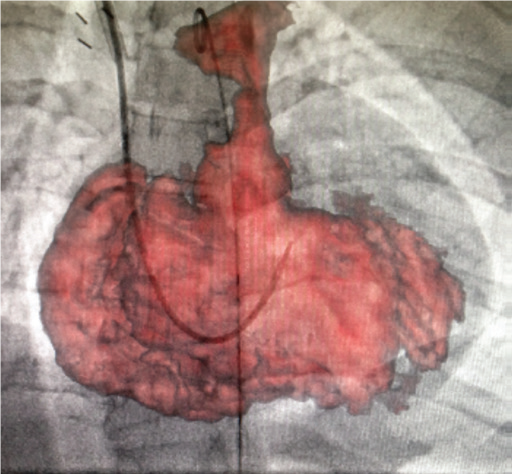

Програмне забезпечення MM Roadmap (або Multi-modality fusion) забезпечує додаткову інформацію завдяки 3D-візуалізації судинної анатомії, що успішно використовується при плануванні та навігації транскатетерної заміни клапану для лікування вроджених вад серця.

MM Roadmap дозволяє суміщувати 2D-флюороскопічні зображення з раніше отриманим 3D-об’ємом. Це може бути КТ або МРТ об’єм при чому незалежно від виробника сканера, або з ангіографічної системи Canon.

Суміщене зображення на моніторі змінюватиметься синхронно в залежності від нахилу С-арки, зміни SID, поля огляду, висоти та положення деки столу.

Можливість використання програмного забезпечення MM Roadmap під час складних втручань допомогає скоротити тривалість опромінення та об’єм введеної контрастної речовини..